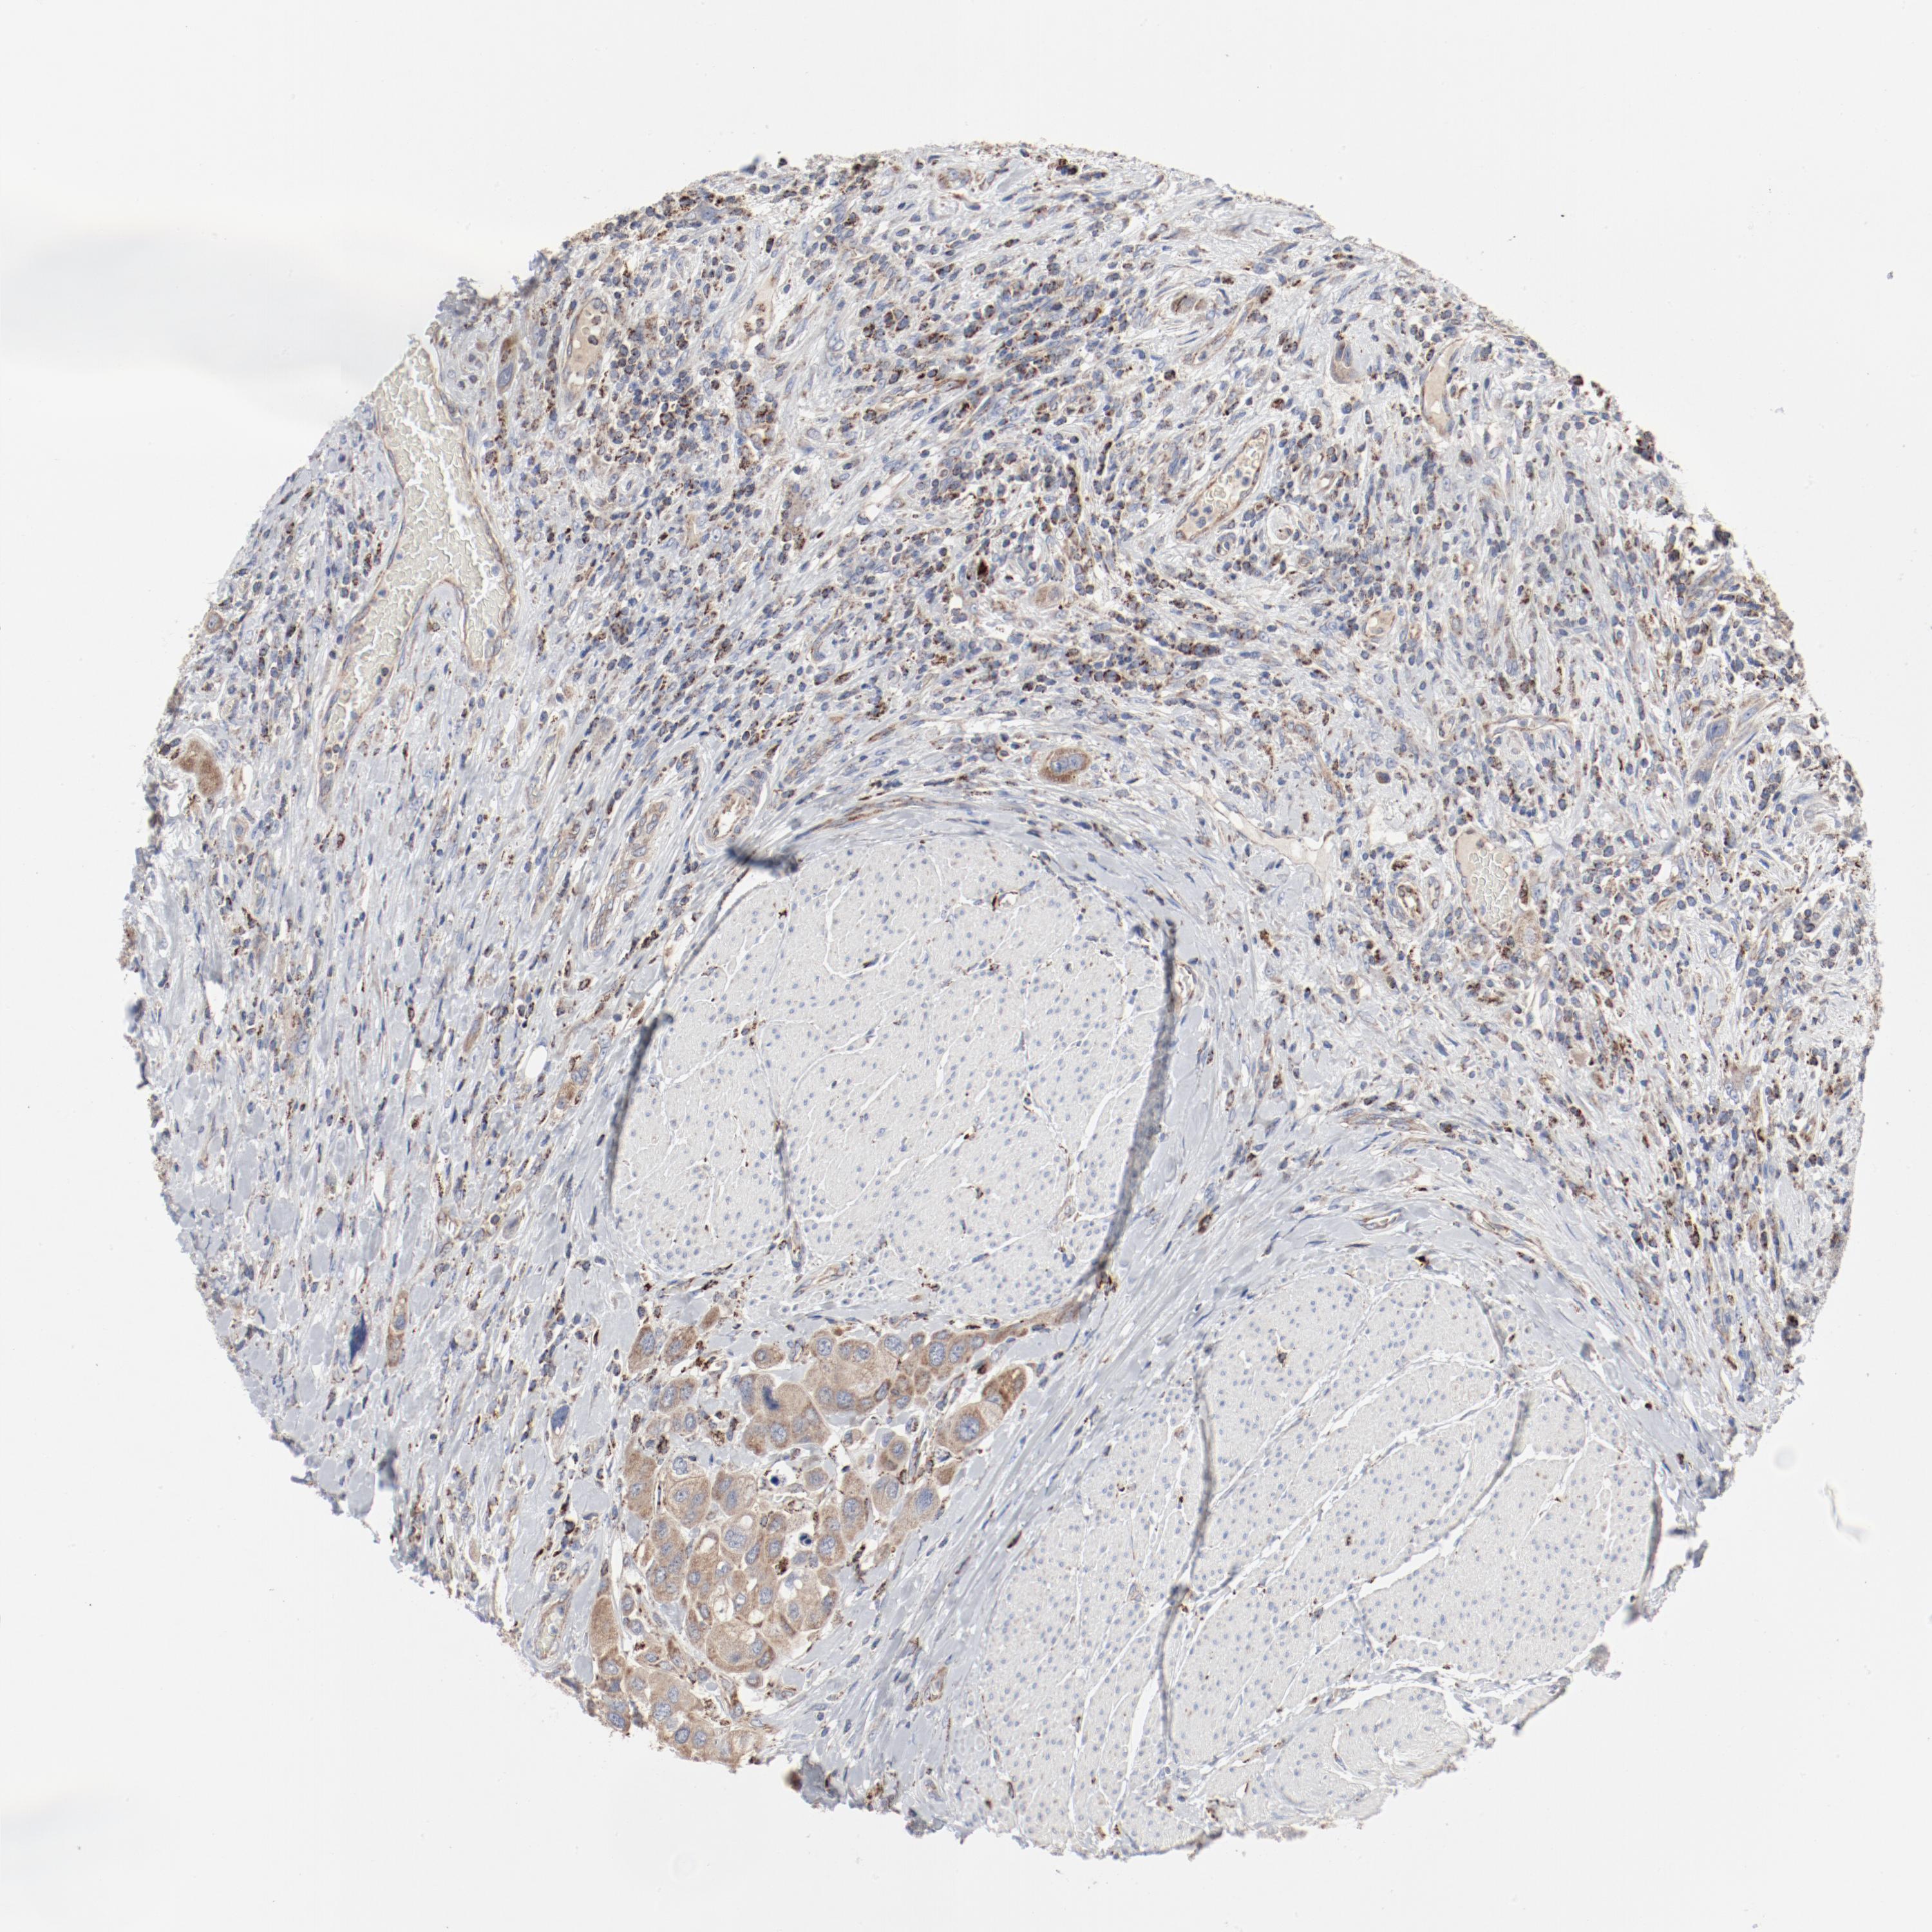

UROTHELIAL CANCER - Protein expressioni

A mouse-over function shows sample information and annotation data. Click on an image to view it in a full screen mode. Samples can be filtered based on level of antibody staining by selecting one or several of the following categories: high, medium, low and not detected. The assay and annotation is described here.

Note that samples used for immunohistochemistry by the Human Protein Atlas do not correspond to samples in the TCGA dataset.

Antibody stainingi

Antibody staining in the annotated cell types in the current human tissue is reported as not detected, low, medium, or high, based on conventional immunohistochemistry profiling in selected tissues. This score is based on the combination of the staining intensity and fraction of stained cells.

Each image is clickable and will lead to virtual microscopy that enables deeper exploration of all samples and also displays staining intensity scores, fraction scores and subcellular localization as well as patient and tissue information for each sample.

Antibody HPA003591

Antibody HPA003639

Staining

High

Medium

Low

Not detected

Intensity

Strong

Moderate

Weak

Negative

Quantity

>75%

75%-25%

<25%

None

Location

Nuclear

Cytoplasmic/membranous

Cytoplasmic/membranous,nuclear

Urothelial carcinoma, High grade

Urothelial carcinoma, Low grade